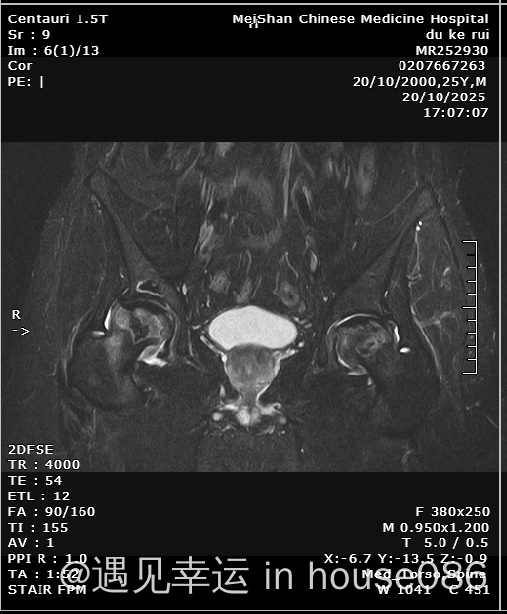

问四川有无好的的中医,治疗结疗后想巩固疗效,霍奇金淋巴瘤结疗半年又发现股骨头坏死